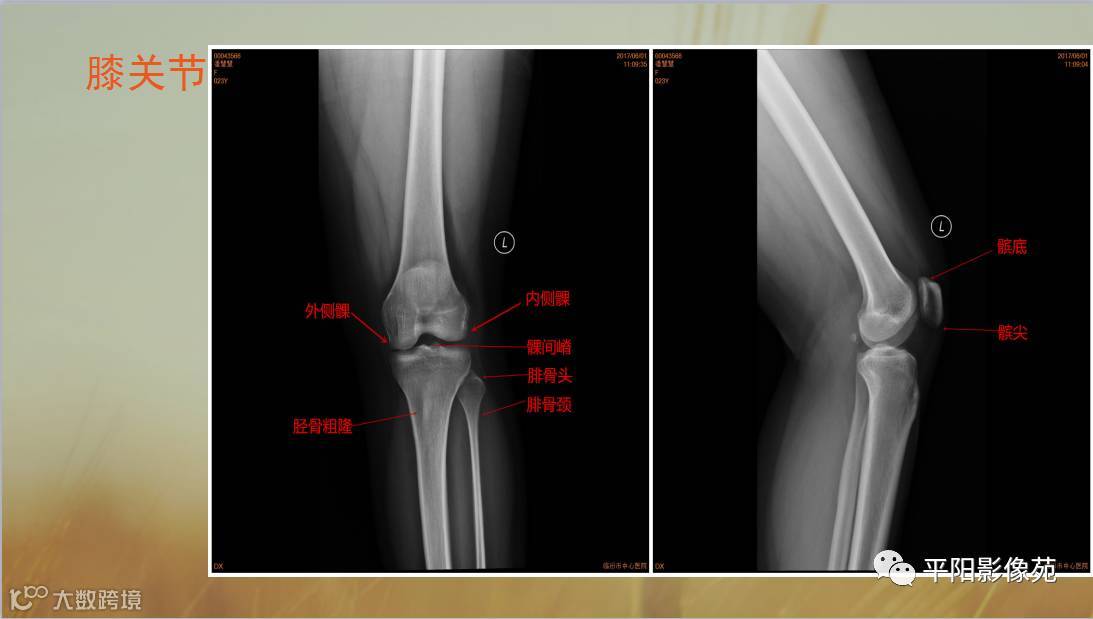

四肢骨骼X线解剖